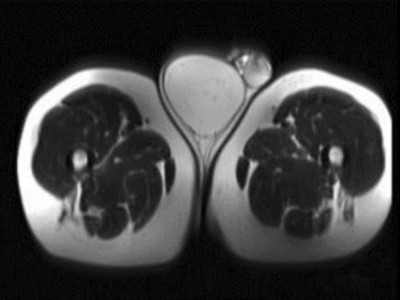

Seltener Befund: Als Skrotalhernie getarnter maligner Tumor

Ein 63-jähriger Patient stellte sich mit einer seit 8 Monaten größenprogredienten Raumforderung im rechten Skrotum ambulant urologisch vor. Er habe keine Schmerzen, sei aber inzwischen deutlich eingeschränkt in der Bewegung und insbesondere beim Sitzen, was seine berufliche Tätigkeit als Baggerfahrer unmöglich mache. Wie lautet Ihre Diagnose?